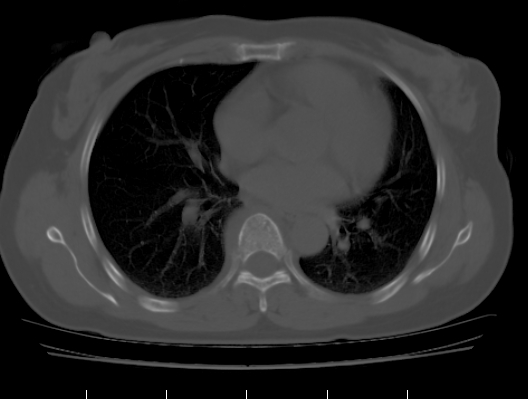

标题: CT25227:背部疼痛伴双侧胸壁痛2月,食欲差。 [打印本页]

标题: CT25227:背部疼痛伴双侧胸壁痛2月,食欲差。

肺结核并胸椎结核?请各位高手指教。

用椎体的条件来扫胸椎呀!考虑1左侧胸膜小结节形成2椎体结核并冷脓肿形成

左肺结核灶,胸椎结核并冷脓肿。

左肺结核灶,胸椎结核并冷脓肿